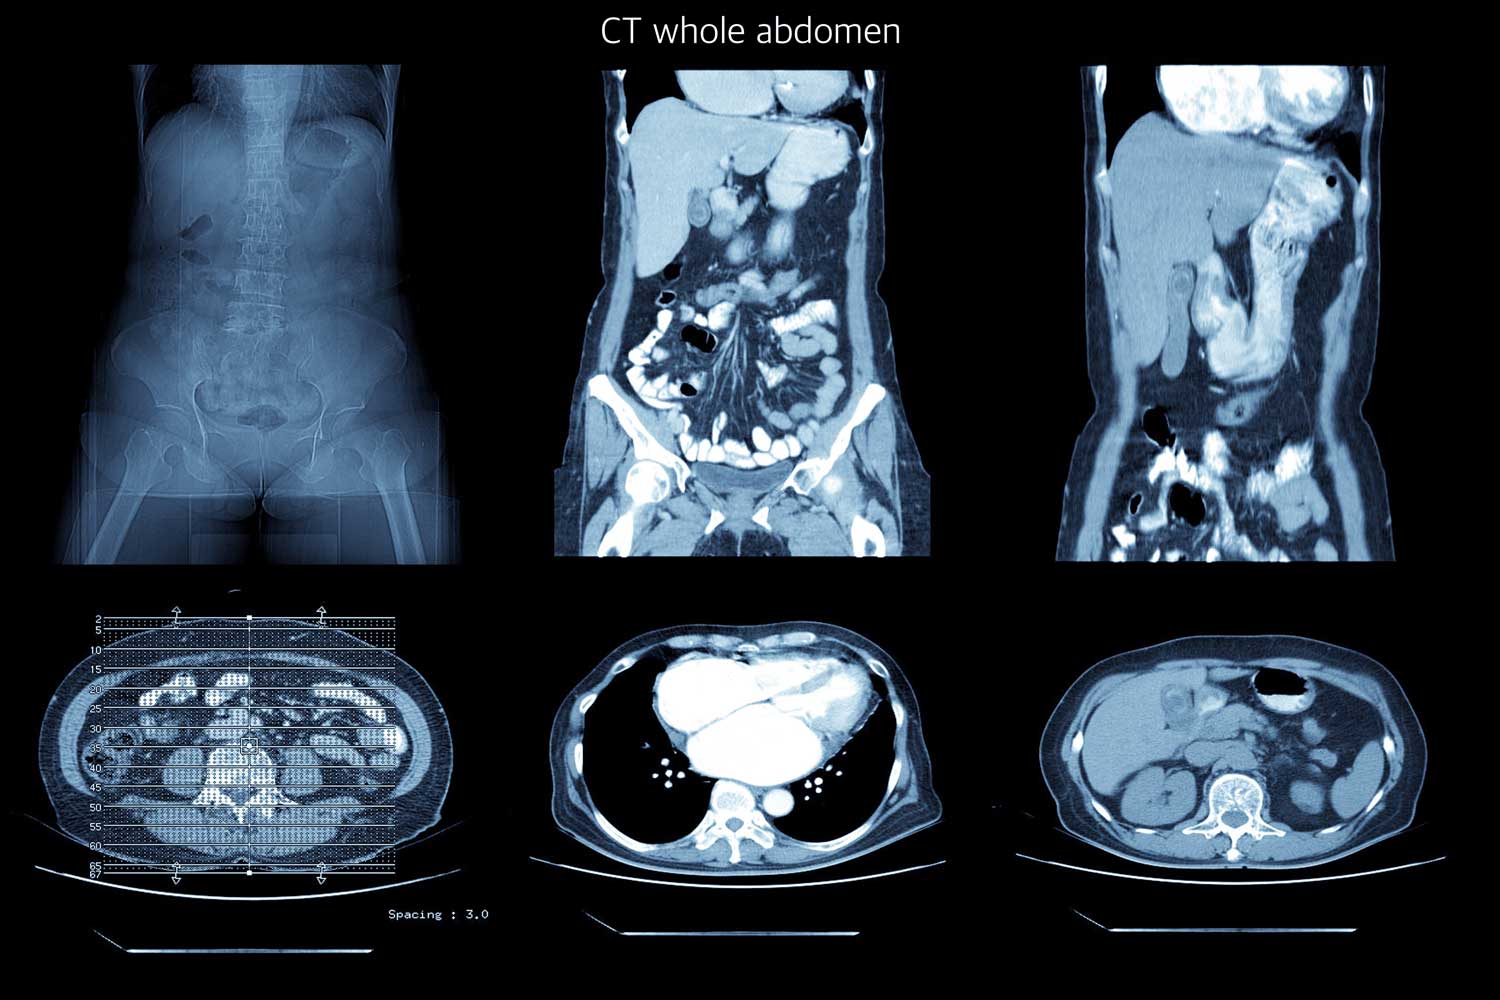

A CT scan (computed tomography, also called a CAT scan) uses a rotating X-ray beam and a computer to produce detailed cross-sectional images of the inside of your body. Unlike a standard X-ray, which takes a single flat picture, a CT scanner captures images from many different angles and combines them to create layered “slices” that can be viewed individually or reconstructed into three-dimensional images.

An abdominal CT scan specifically images the structures between your diaphragm and your pelvis, including the liver, gallbladder, spleen, pancreas, kidneys, adrenal glands, stomach, small and large intestines, appendix, abdominal aorta, inferior vena cava, and the lymph nodes and fat tissue that surround them. In many cases, the scan also extends to include the pelvic organs (bladder, reproductive organs, and rectum), which is called an abdomen and pelvis CT.

A board-certified radiologist at IPMC will analyze every image from your scan and prepare a comprehensive report. Here are some of the things your radiologist evaluates:

Organ size and appearance. The liver, spleen, kidneys, pancreas, and adrenal glands are each assessed for normal size, shape, and density. Enlargement, shrinkage, or abnormal density can indicate disease.

Masses, tumors, and cysts. Any abnormal growths are identified, measured, and characterized based on their appearance and enhancement pattern with contrast. Many cysts and benign masses have a characteristic CT appearance that allows confident diagnosis without biopsy.

Kidney stones. Stones appear as bright white spots on non-contrast CT. The radiologist documents their size, location (kidney, ureter, or bladder), and whether they are causing obstruction (hydronephrosis).

Inflammation and infection. Signs of appendicitis, diverticulitis, pancreatitis, cholecystitis, and other inflammatory conditions are identified based on organ swelling, fat stranding (haziness of the surrounding fat), fluid collections, and wall thickening.

Bowel abnormalities. The small and large intestines are evaluated for obstruction, perforation, thickening, masses, and diverticular disease.

Blood vessels. The aorta and other major vessels are assessed for aneurysms, calcification, blood clots, and narrowing.

Lymph nodes. Enlarged lymph nodes may suggest infection, inflammation, or cancer.

Incidental findings. CT scans sometimes reveal unexpected findings unrelated to your symptoms — such as a small kidney cyst or a benign adrenal nodule. Your doctor will explain these findings and whether any follow-up is needed.